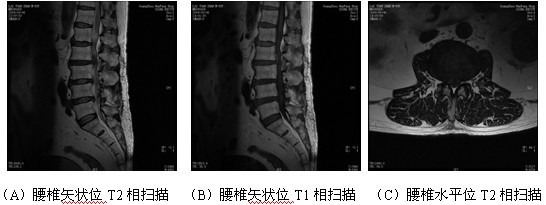

图2 腰椎MRI扫描

(L4椎体后方棘突呈术后改变,局部软组织层次较模糊。腰骶椎生理曲度变直,各椎体前后缘毛糙、变尖,L2/3~L5/S1椎间隙变窄,横断面示L1/2间盘后缘轻度向后方膨出,L4/5间盘后缘局限向正中突出,并压迫硬膜囊,双侧侧隐窝轻度变窄,硬膜外脂肪消失。L2/3间盘向后方脱出,双侧侧隐窝明显变窄,神经根显示不清,同层面椎管前后径狭窄。)